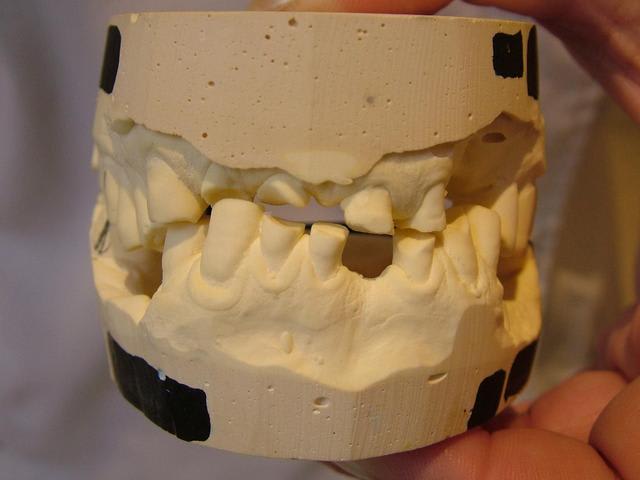

Je joins les photos des modèles avec l'occlusion que le patient semble donner.

Antérieur ebx818 - Eugenol

Côté droit hzhelg - Eugenol

Côté droit rlu6he - Eugenol

Côté gauche hvjxyj - Eugenol

Voilà la suite

Antérieur v4bbqp - Eugenol

Côté droit fac9tb - Eugenol

peut-être la fin ; il en reste deux !

Antérieur qrykzz - Eugenol

Pano xxztry - Eugenol

Antérieur vpje6p - Eugenol